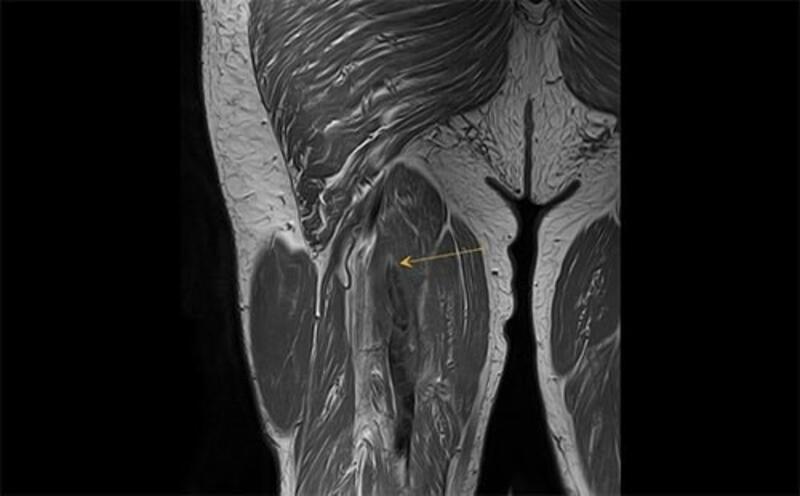

Al respecto, el doctor Mostien y sus compañeros del Hospital Jessa (en Hasselt-Bélgica) y la Universidad de Hasselt tomaron biopsias musculares de pacientes con Covid en estado crítico antes y después de la admisión a cuidados intensivos. Un total de 18 pacientes fueron analizados para el proyecto. Concretamente su vasto lateral, el músculo más grande y poderoso del muslo, biopsiado varias veces desde 1-3 días antes de la admisión en la UCI hasta 5-8 días después de la admisión. Los pacientes tenían una edad media de 69 años y el 82 por ciento eran hombres.